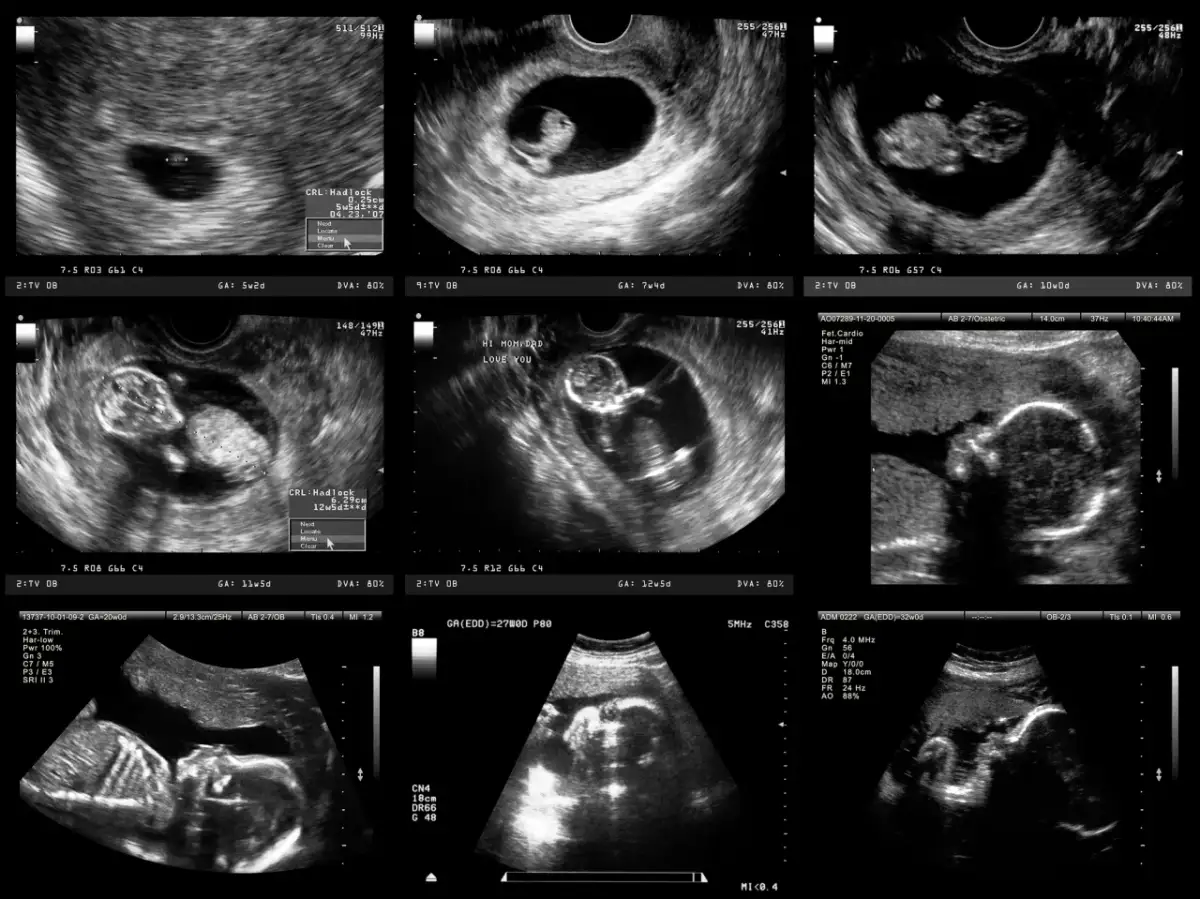

Często spotykam się z pytaniem, czy pierwsze USG, wykonywane jeszcze przed 10. tygodniem ciąży, jest absolutnie niezbędne. Chociaż zgodnie z oficjalnym standardem opieki okołoporodowej nie jest ono badaniem obowiązkowym, to jednak Polskie Towarzystwo Ginekologów i Położników zdecydowanie je rekomenduje. W praktyce jest to badanie powszechnie wykonywane i, moim zdaniem, niezwykle cenne. Pozwala ono na wczesne potwierdzenie ciąży i daje spokój ducha na jej początkowym etapie.

Głównym celem tego wczesnego badania USG jest przede wszystkim potwierdzenie samej ciąży i jej prawidłowej lokalizacji w macicy. To kluczowe, aby wykluczyć ciążę pozamaciczną, która jest stanem zagrożenia życia kobiety. Podczas tego badania możemy również ocenić liczbę zarodków dowiedzieć się, czy spodziewasz się jednego, czy może więcej dzieci. Co więcej, wczesne USG pozwala nam uwidocznić czynność serca płodu, co jest niezwykle wzruszającym i uspokajającym momentem dla przyszłych rodziców. Na podstawie pomiaru długości ciemieniowo-siedzeniowej (CRL) możemy również wstępnie określić wiek ciążowy, co jest punktem wyjścia do dalszego monitorowania.

USG I trymestru to pierwsze obowiązkowe i refundowane przez NFZ badanie przesiewowe, które ma ogromne znaczenie dla wczesnej diagnostyki. Wykonujemy je w ściśle określonym czasie między 11. tygodniem i 0 dniem a 13. tygodniem i 6 dniem ciąży (czyli 11+0 do 13+6 tygodnia). Ten krótki, ale precyzyjny okres jest kluczowy, ponieważ pozwala nam na optymalną ocenę wielu ważnych parametrów.

USG I trymestru jest najbardziej precyzyjne do określenia wieku ciążowego i co za tym idzie, ostatecznego terminu porodu. Na tym etapie wszystkie płody rozwijają się w bardzo podobnym tempie, co pozwala nam na dokładne datowanie ciąży na podstawie pomiaru długości ciemieniowo-siedzeniowej (CRL).

Wielkie badanie w połowie drogi: USG połówkowe (18-22 tydzień)

Zbliżamy się do finiszu! USG III trymestru to trzecie obowiązkowe i refundowane przez NFZ badanie, które wykonujemy między 28. a 32. tygodniem ciąży. Na tym etapie dziecko jest już znacznie większe, a my skupiamy się na innych, równie ważnych aspektach jego rozwoju i przygotowania do porodu.